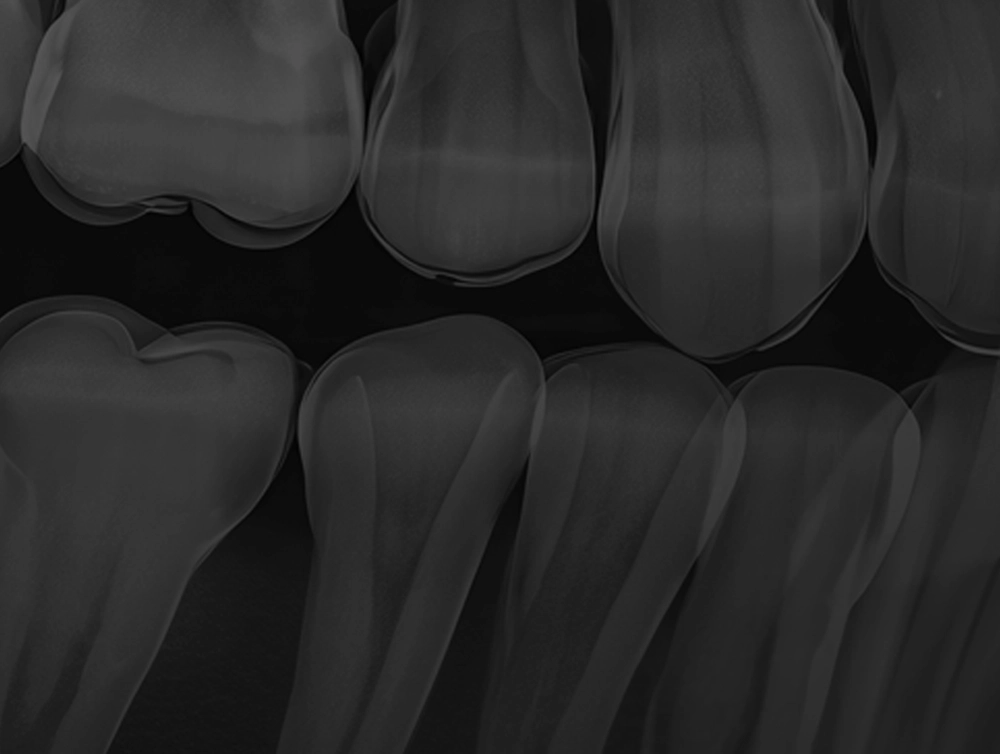

「ぶつけた覚えがないのに歯が欠けた」「奥歯の表面に黒い穴が見える」「ズキズキとした痛みを感じる」──そんな小さな変化に気づいたら、虫歯のサインかもしれません。

虫歯は進行具合によって、症状や必要な治療が大きく異なります。痛みが出てからでは大がかりな治療が必要となるケースもあるため、早めの発見・対応が大切です。当院では、進行度に応じた適切な治療をご提案しています。

検査・診断まずは患者様のお悩みやご希望を丁寧にヒアリングし、レントゲンや口腔内写真、歯周病・噛み合わせなどの検査を通じて、現在のお口の状態を詳しく把握します。